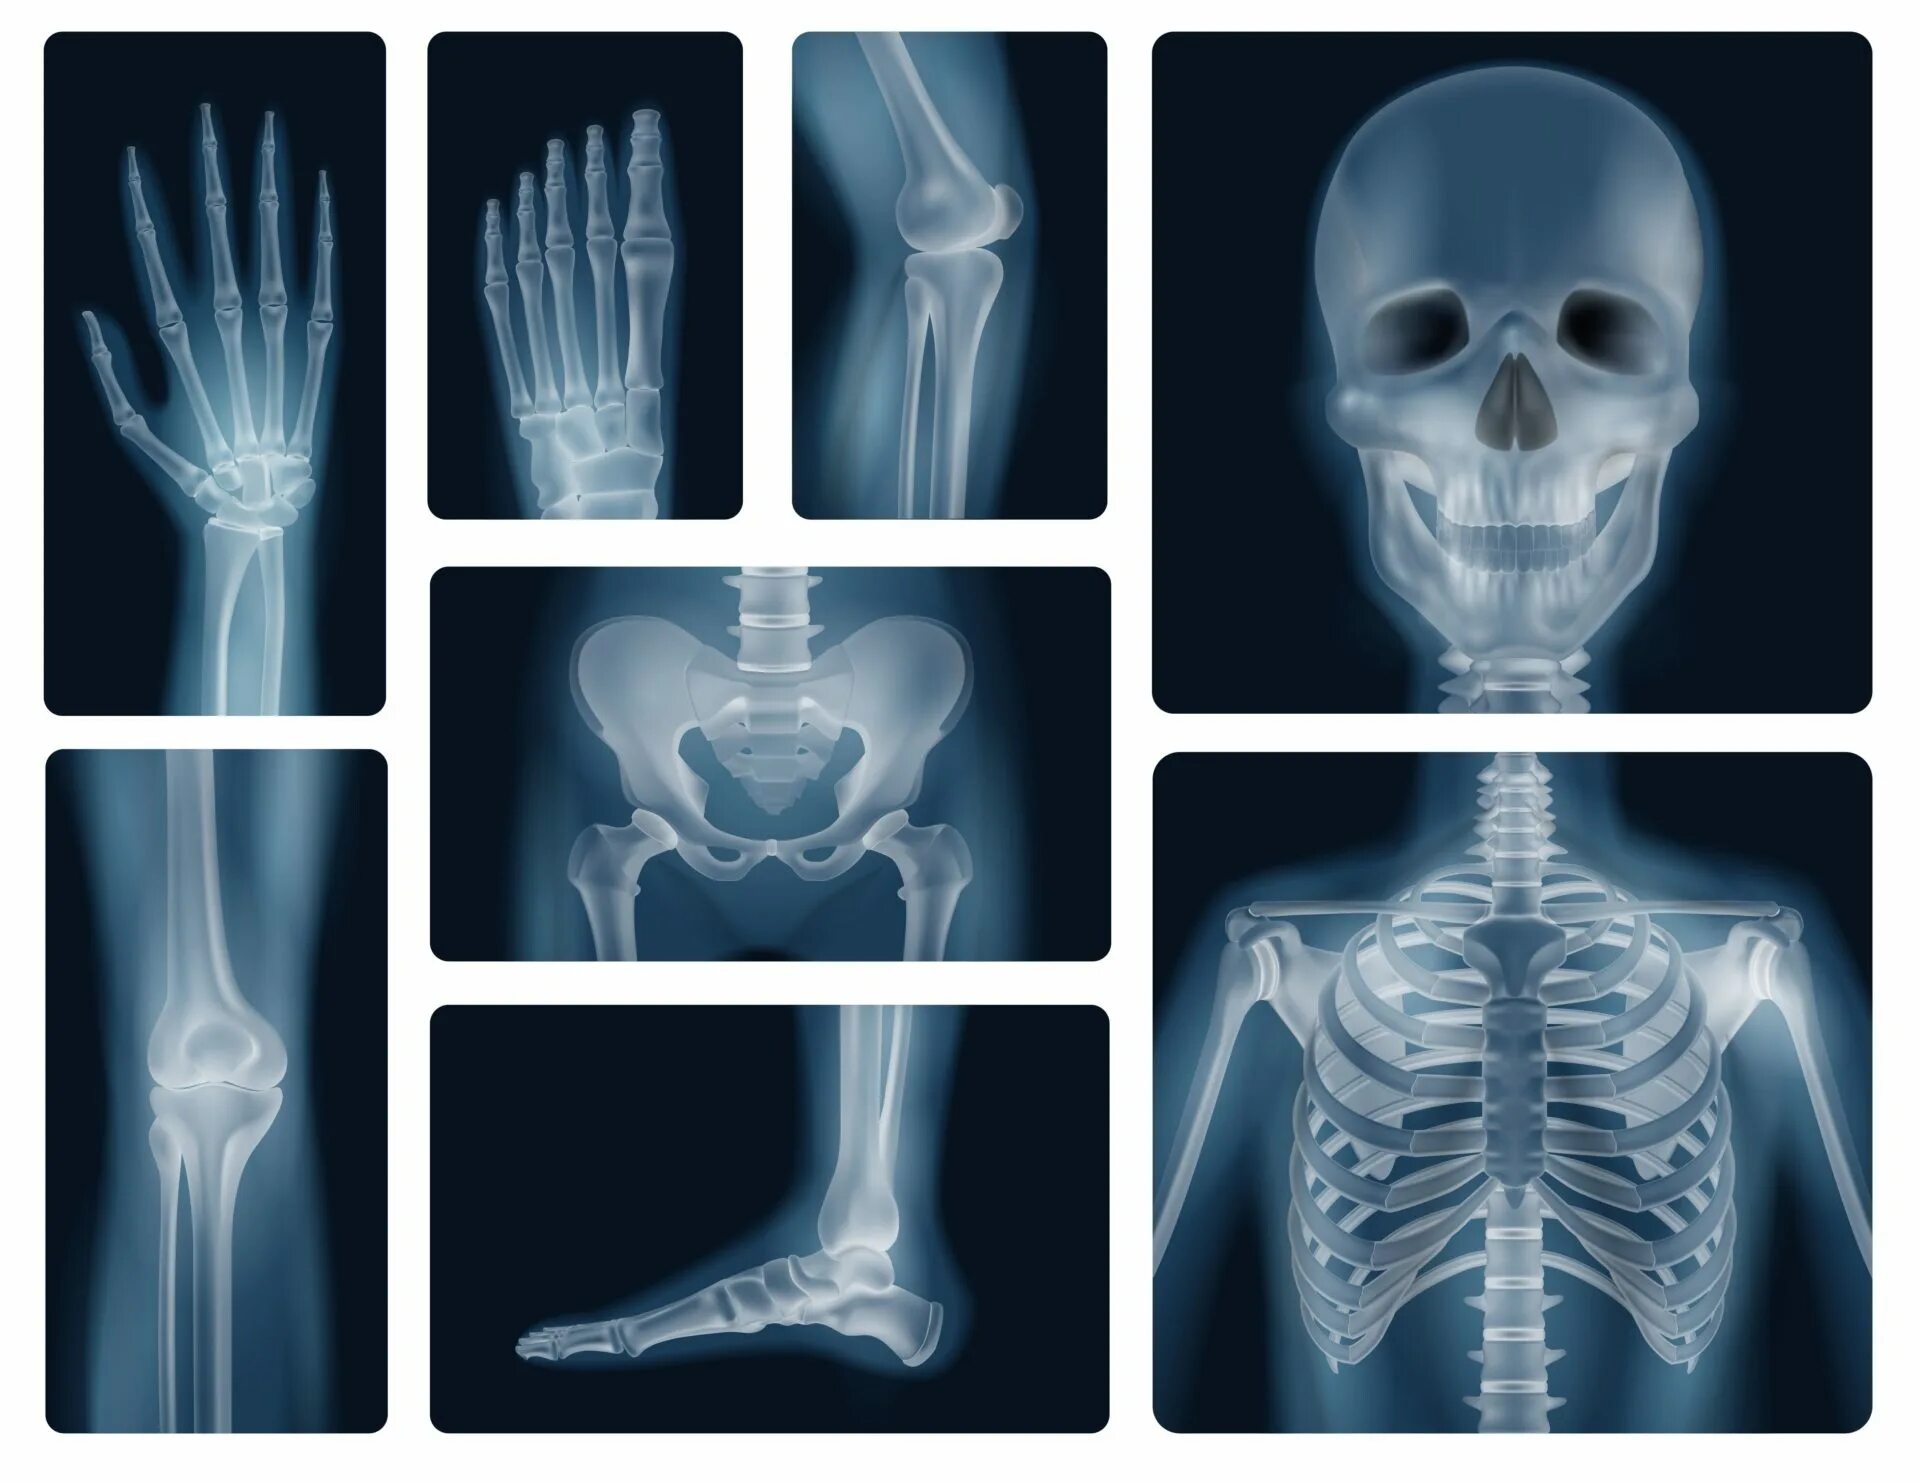

Снимок костей как называется